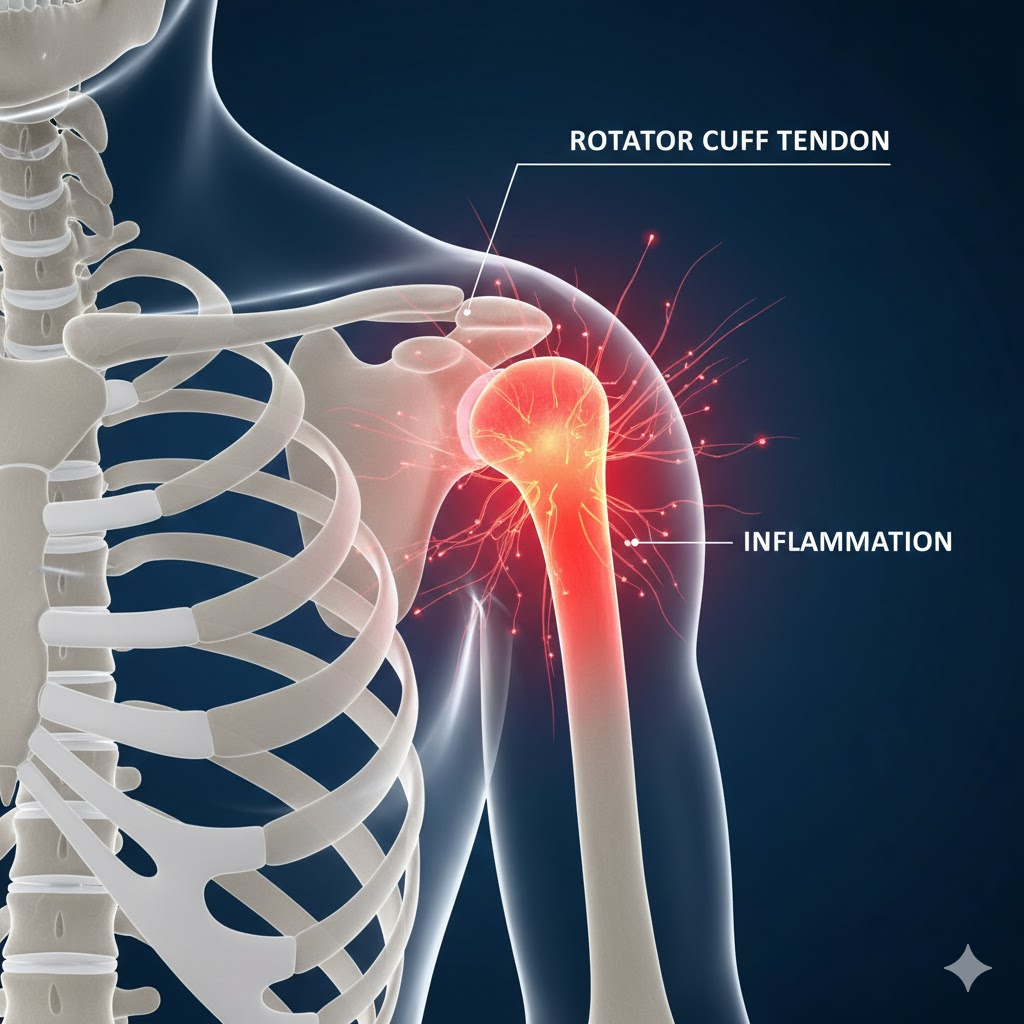

우리가 흔히 '어깨에 돌이 생겼다'라고 표현하는 질환의 정식 명칭은 석회화 건염입니다. 이는 어깨를 움직이는 네 개의 힘줄인 '회전근개' 속에 칼슘 성분이 침착되어 돌처럼 딱딱한 석회가 생기고, 이 과정에서 주변 조직에 염증을 일으키는 상태를 말합니다.

건강보험심사평가원 자료에 따르면, 석회화 건염은 주로 40대에서 60대 사이에서 빈번하게 발생합니다. 정확한 원인은 아직 명확히 밝혀지지 않았지만, 힘줄의 노화(퇴행성 변화), 혈액 공급의 감소, 혹은 어깨의 과도한 사용으로 인한 미세 손상과 관련이 깊은 것으로 알려져 있습니다.

석회는 생성되는 시기보다 오히려 '흡수되는 시기'에 통증이 훨씬 심해지는 특징이 있습니다. 몸이 석회를 이물질로 인식하여 녹여서 흡수하는 과정에서 강력한 염증 반응이 일어나기 때문입니다. 따라서 현재 극심한 통증을 겪고 있다면, 이는 적절한 어깨 석회질치료방법이 필요한 단계에 와 있다는 신호입니다.